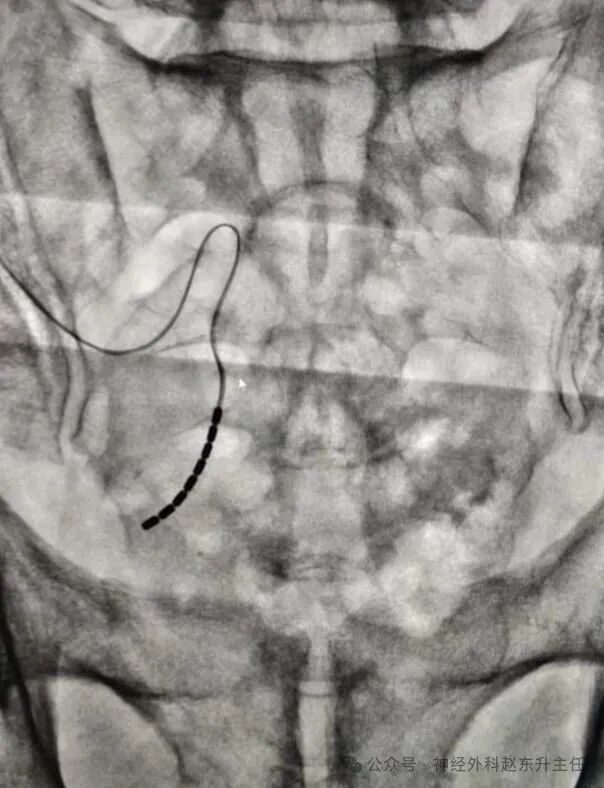

IMG_20250515_150954.jpg

脊髓电刺激外科电极位置